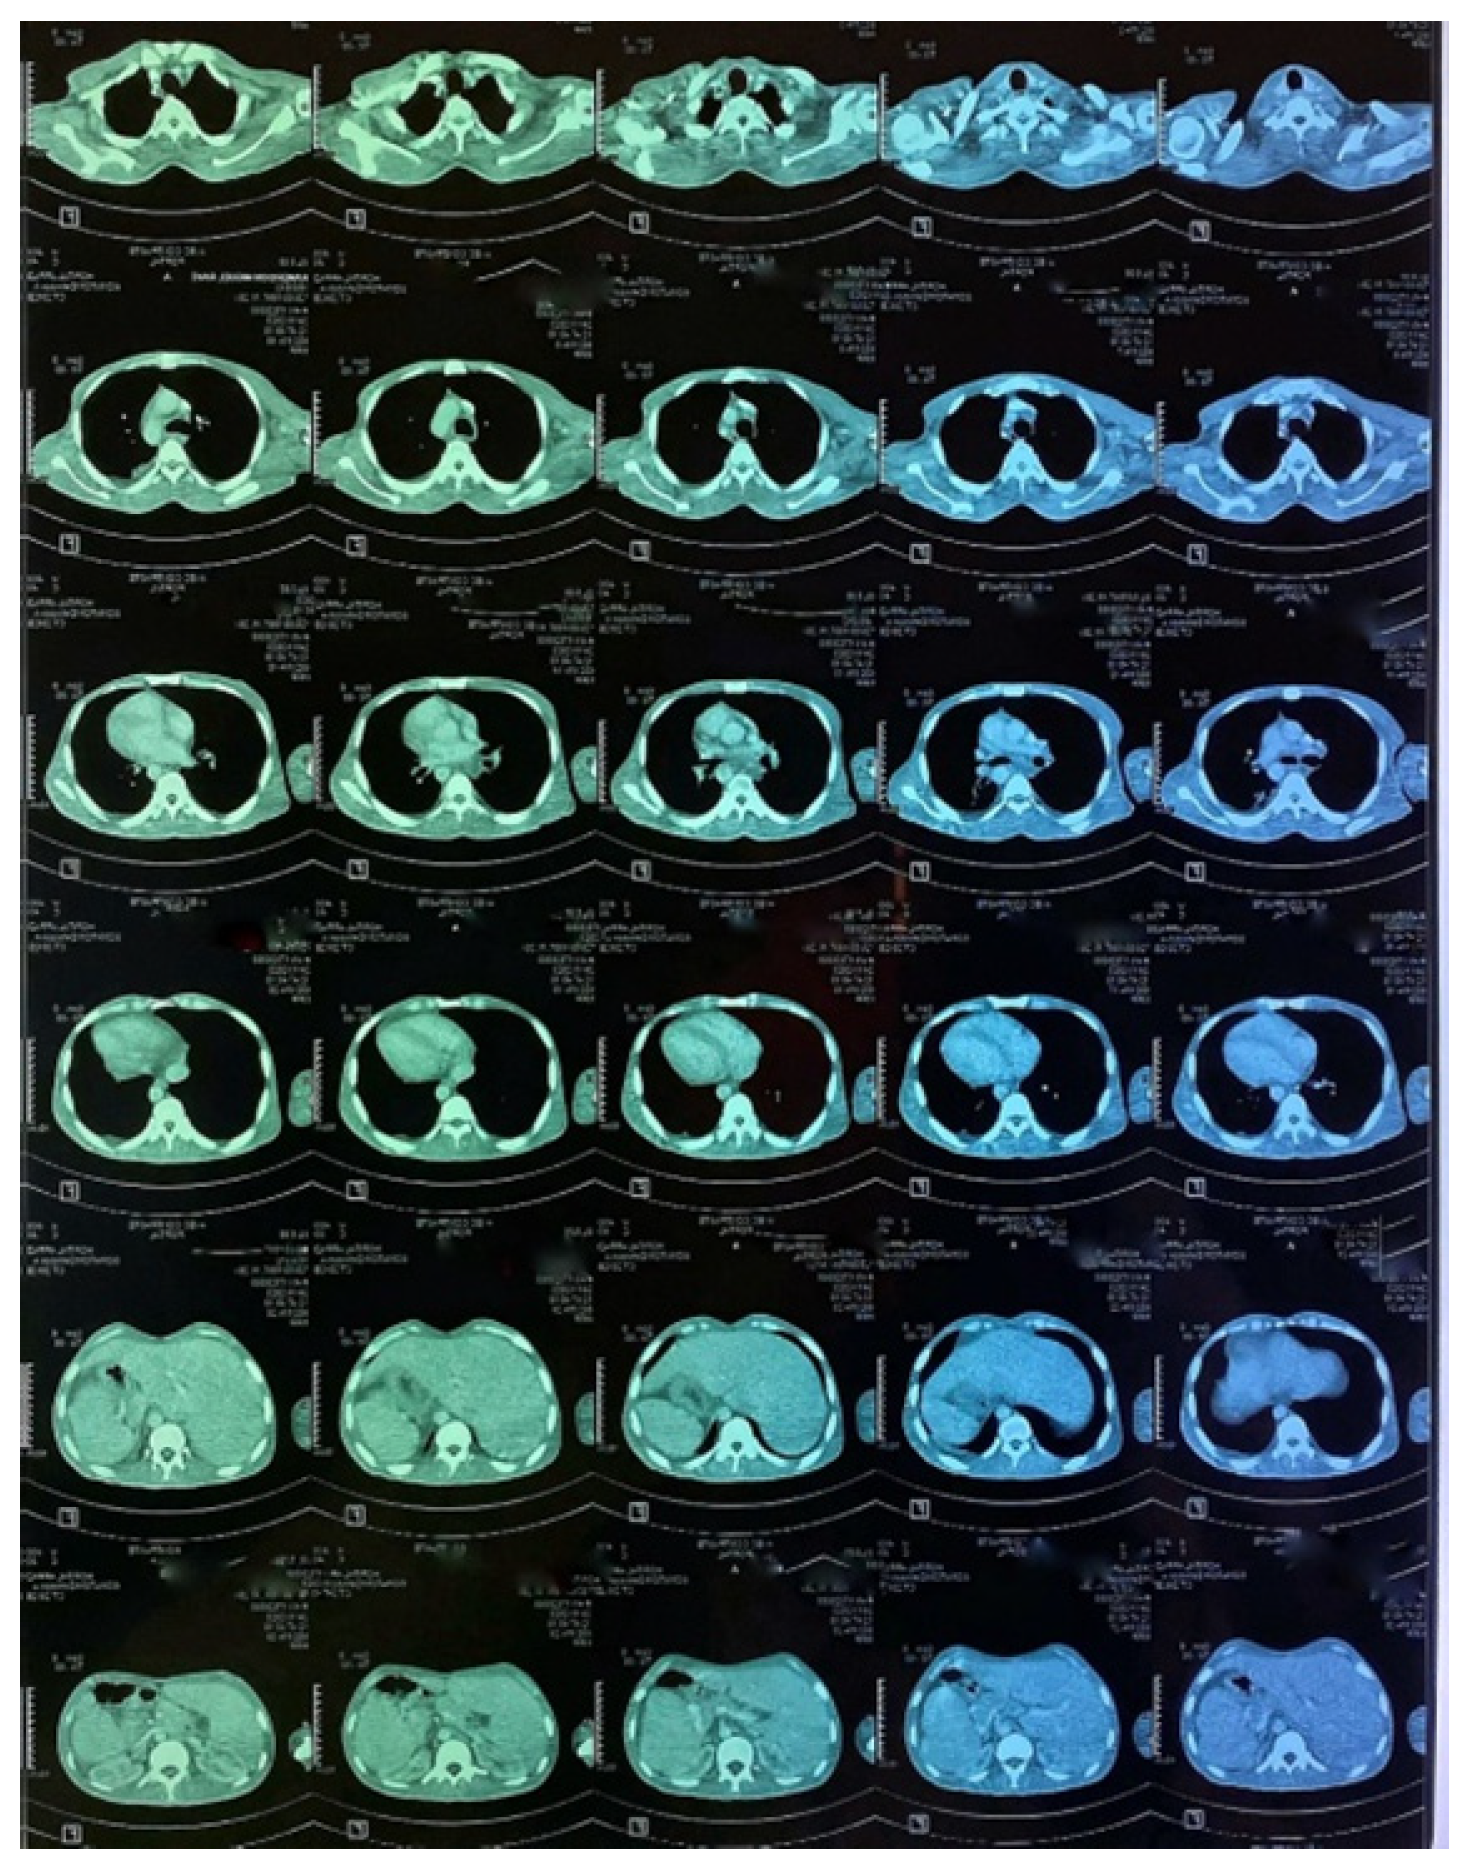

Figure 6. CT images of the thorax and abdomen:axial view.

Figure 7. CT images of the thorax and abdomen.

A CT scan of the chest, abdomen and pelvis was subsequently performed, showing a mild left pleural and abdominal effusion associated with right supra-diaphragmatic adenopathy and homogeneous hepatosplenomegaly (Figure 6 and Figure 7).